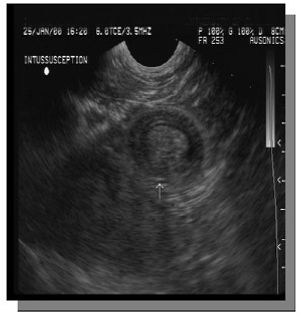

Abdominal pain in the foal can be a frustrating diagnostic challenge as the differential diagnosis are extensive.